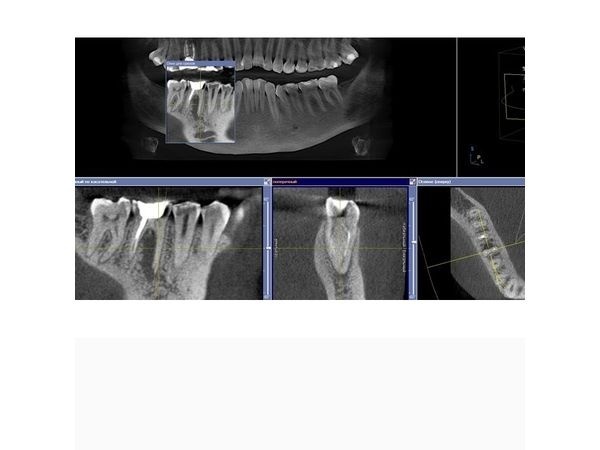

КЛКТ челюстно-лицевой области выявила очаг хронического воспаления в области верхушки мезиального (левого) корня зуба 1.6, второй мезио-букальный корневой канал (второй канал слева, ближе к щеке) был не запломбирован (пропущен).

В области мезиального корня зуба 4.6 отмечался обширный очаг разрушения кости, который распространялся от верхушки корней до места их соединения, тень пломбировочного материала в мезиальных корневых каналах нечёткая и неоднородная, располагалась пристеночно, доходила до половины и второй трети каналов (мезиального и дистального).